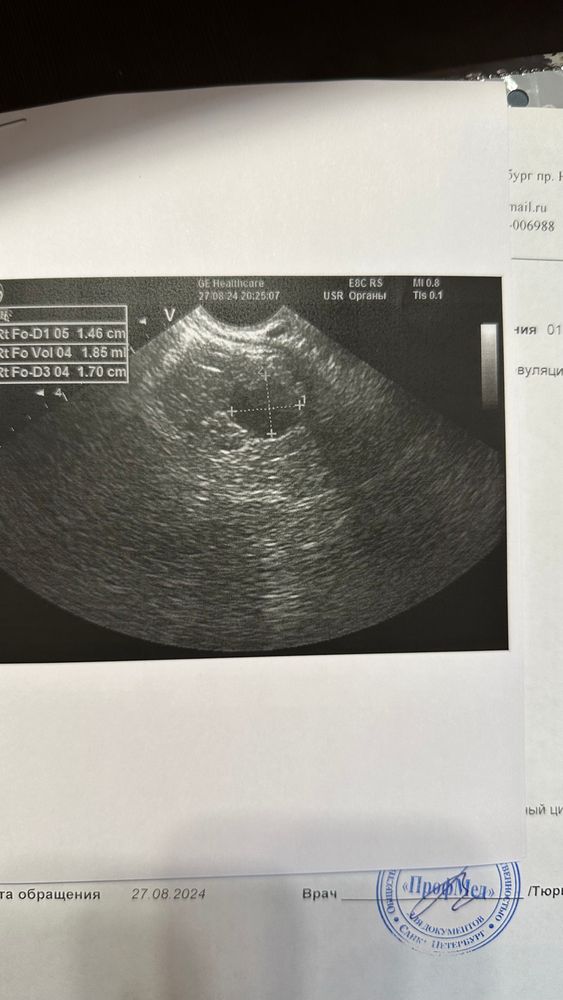

Была на узи на 22 дц, ДФ был 14 мм, эндометрий 1 см, на 25 дц тест на овуляций прям горел, потом через 3 дня начались прогестероновые выделения. Сегодня на 31 дц сходила на фолликулометрию, уже 5 дпо, жидкости нет, сказали, что теоретические ее уже может и не быть на 5 дпо, эндометрий 1 см, и под самый конец узи врач нашла типа дф 17 мм. Не понимаю как такие выделения если не было овуляции и как дф вырос только на 3 мм за 10 дней. Васкуляризацию не смотрела, и теперь сижу и гадаю могла ли она перепутать дф с жт? Поделитесь своими историями🙏❤️

Екатерина , грош цена такому узисту. Эндометрий описывают, при осмотре доминанта включают цдк, кровоток смотрят. Их путают с кистозным жт. Мое жт